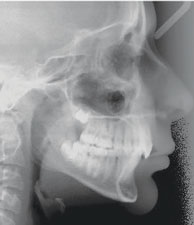

Figs. 3a-g: Initial records.

Fig. 3a

Fig. 3b

Fig. 3c

Fig. 3d

Fig. 3e

Fig. 3f

Fig. 3g